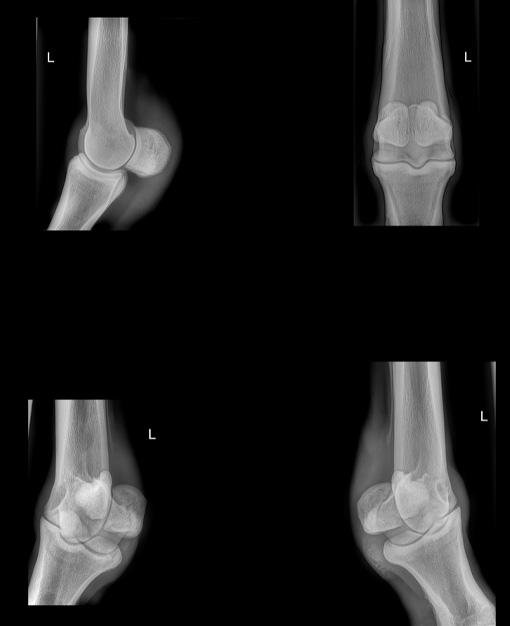

Radiography revealed remodelling within both stifles and a clear OCD lesion within the right femoropatellar joint.

Arthroscopy:

The left stifle showed severe inflammatory changes, consistent with established OA, a large OCD lesion on the lateral trochlear ridge and multiple areas of cartilage damage. The right stifle also showed significant inflammatory changes, with several areas of abnormal cartilage appearance and focal lesions.